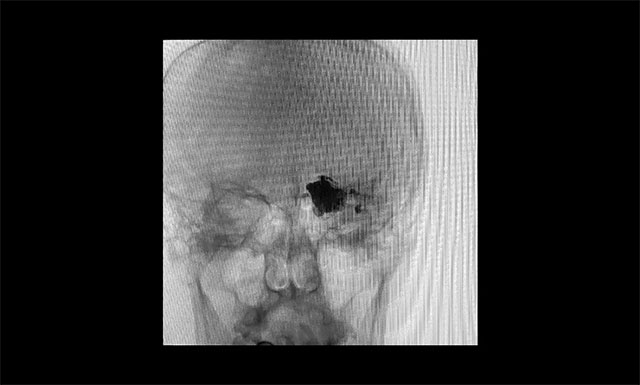

術(shù)畢左側(cè)頸內(nèi)動脈造影

▲ 術(shù)畢左側(cè)頸內(nèi)動脈造影

術(shù)畢左側(cè)頸外動脈造影

▲ 術(shù)畢左側(cè)頸外動脈造影

12月6日,患者于全麻下手術(shù)。手術(shù)順利,術(shù)中完全栓塞瘺口,重要的血管保持通暢。術(shù)后,患者牙痛癥狀消失,無新發(fā)功能缺損。